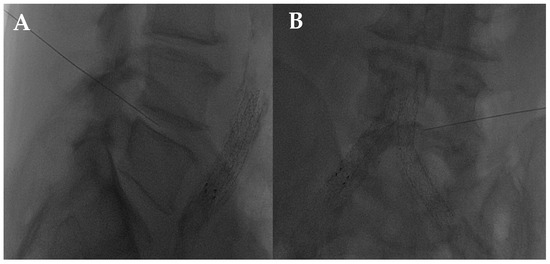

- Napoli, A.; Alfieri, G.; De Maio, A.; Panella, E.; Scipione, R.; Facchini, G.; Albisinni, U.; Spinnato, P.; Nardis, P.G.; Tramutoli, R.; et al. CT-Guided Pulsed Radiofrequency Combined with Steroid Injection for Sciatica from Herniated Disk: A Randomized Trial. Radiology 2023, 307, e221478. [Google Scholar] [CrossRef] [PubMed]